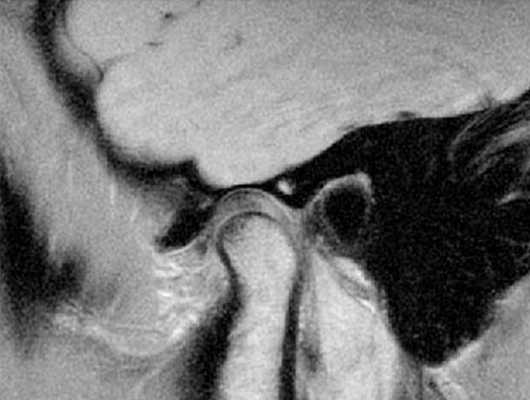

Магнитно-резонансная томография ВНЧС - невправляемый вывих. Стрелкой указано хрящевое образование, которое остается смещенным при закрытом (a) и открытом (b) рте.

На МРТ ВНЧС “застрявший диск” (a - открытый рот, b - закрытый). Стрелкой обозначена задняя поверхность хрящевого образования, которая вне зависимости от движений остается в нижнечелюстной ямке.

При поражении ВНЧС делаютя МРТ с функциональными пробами в следующих положениях: с закрытым ртом, приоткрытым и полностью открытым. Такой подход позволяет визуализировать весь процесс движения в различных проекциях. Используя полученные результаты, врач поймет, в какой момент происходит сбой.

В норме кости не соприкасаются, но патологическая подвижность диска приводит к трению и болезненным ощущениям. Последний может изменять положение в различных направлениях, наиболее распространено переднее смещение.

Примером еще одной патологии, которую помогают установить функциональные пробы, является фиксированный, перемежающийся вывих и подвывих. Специалист увидит на изображении с закрытым ртом смещение внутрисуставного образования, а в открытом состоянии оно вернется на место. Описанный результат будет свидетельствовать о перемежающемся вывихе челюстного сочленения.